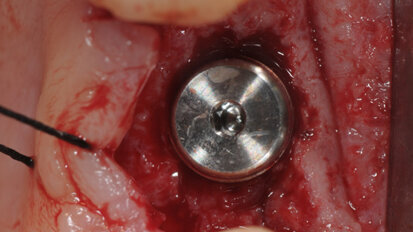

Impianti short a carico immediato in grave atrofia mandibolare

La chirurgia ricostruttiva preimplantare non può essere praticata in tutti i pazienti a causa di possibili controindicazioni locali e/o sistemiche. ...